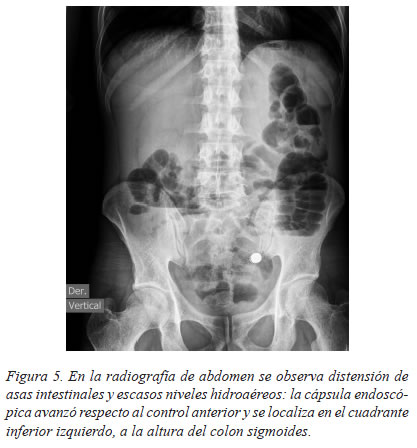

Se practicó una radiografía de abdomen que mostró distensión de asas intestinales y escasos niveles hidroaéreos; la cápsula endoscópica se encontraba en el cuadrante inferior izquierdo, lo que sugería su desplazamiento hacia el colon sigmoides (figura 5).